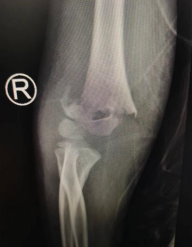

受伤时X光片

图片里右手出现变形、屈伸僵硬的小朋友叫轩轩,今年6岁多,本来已经准备上一年级了。结果半年前,他和小伙伴玩耍时摔倒导致了肱骨髁上骨折,还好就医及时,紧急处理后在家休养了一个月,骨折恢复的差不多了。以为养好骨折孩子就没事了,谁知道虽然骨折好了,但轩轩的右手却出现了“爪形手”、麻木、屈伸不能。家长赶忙带到betway在线登陆寻求帮助。